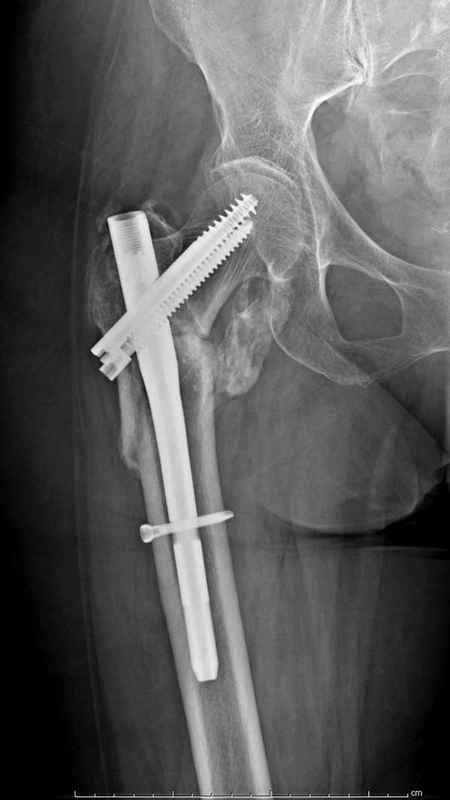

Re: Чрезвертельный перелом бедра

послал Djoldas Kuldjanov 25 Август 2009, 22:19

Здесь 83 года, травма в результате падения